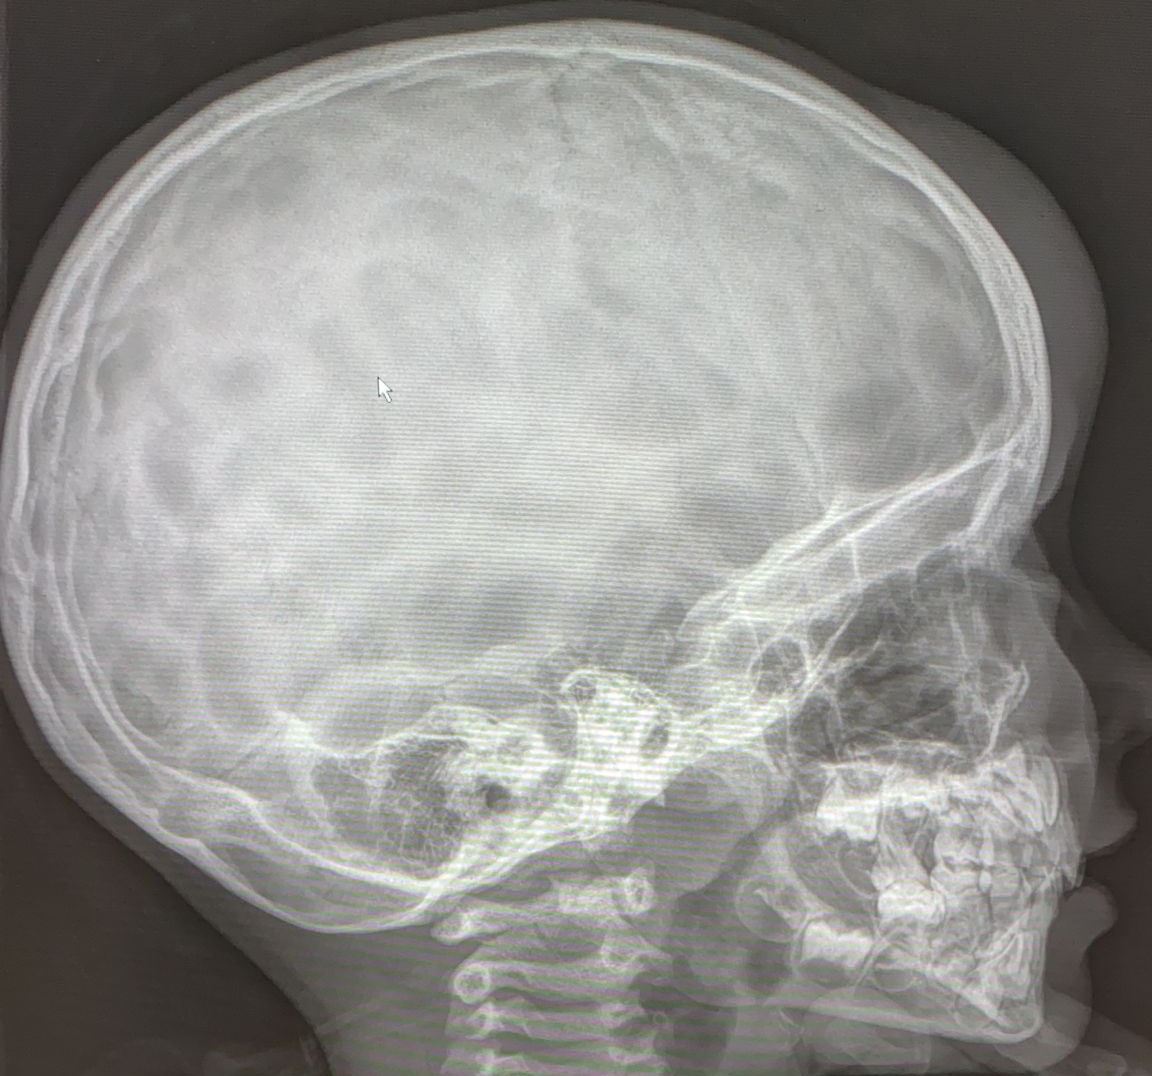

SIGNO DEL ALGODÓN

El signo del algodón hace referencia al aspecto que tiene el hueso en la radiografía de cráneo en pacientes con enfermedad de Paget. Se observa un engrosamiento de la calota en la que existen focos de esclerosis parcheados y de aspecto borroso que resaltan sobre un hueso de menor densidad.